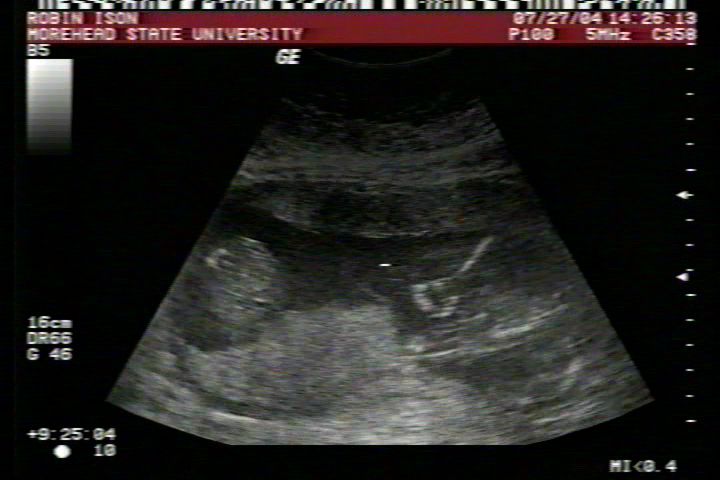

Pictures from Ultrasound at 17 weeks.